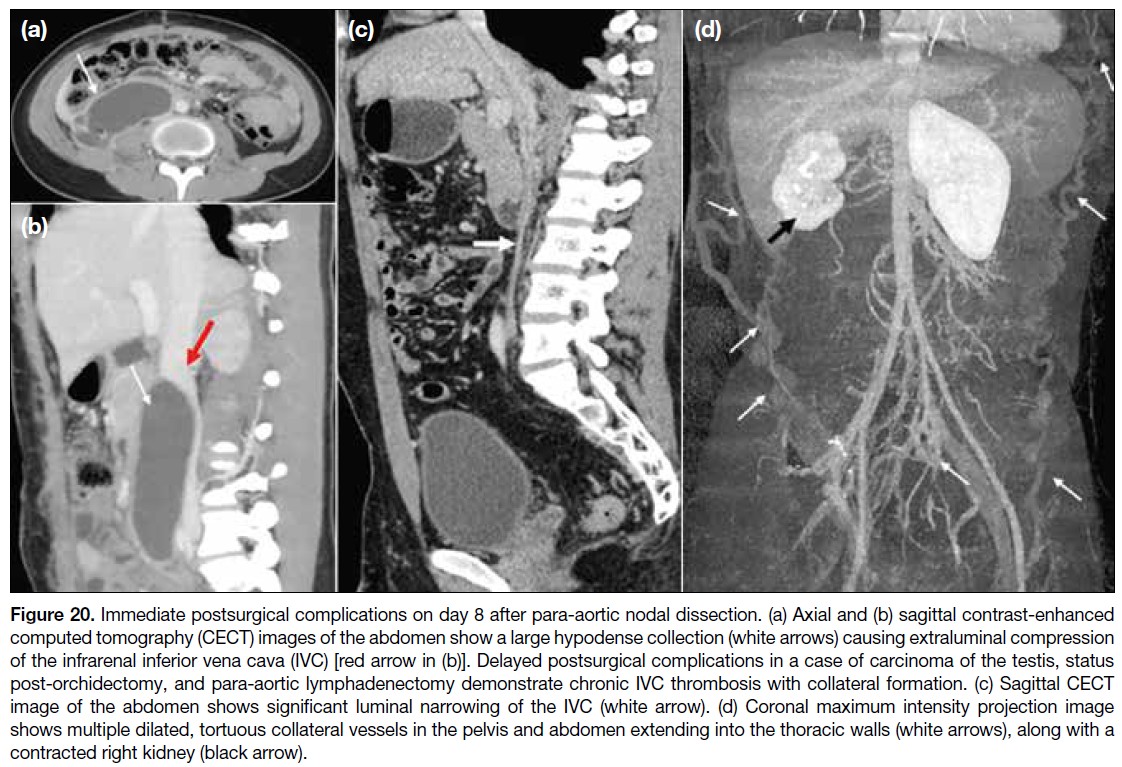

Compression and narrowing of the IVC may occur

as immediate or delayed complications in patients

undergoing extensive retroperitoneal surgeries and

abdominal lymph node dissections (Figure 20).

Figure 20. Immediate postsurgical complications on day 8 after para-aortic nodal dissection. (a) Axial and (b) sagittal contrast-enhanced

computed tomography (CECT) images of the abdomen show a large hypodense collection (white arrows) causing extraluminal compression

of the infrarenal inferior vena cava (IVC) [red arrow in (b)]. Delayed postsurgical complications in a case of carcinoma of the testis, status

post-orchidectomy, and para-aortic lymphadenectomy demonstrate chronic IVC thrombosis with collateral formation. (c) Sagittal CECT

image of the abdomen shows significant luminal narrowing of the IVC (white arrow). (d) Coronal maximum intensity projection image

shows multiple dilated, tortuous collateral vessels in the pelvis and abdomen extending into the thoracic walls (white arrows), along with a

contracted right kidney (black arrow).